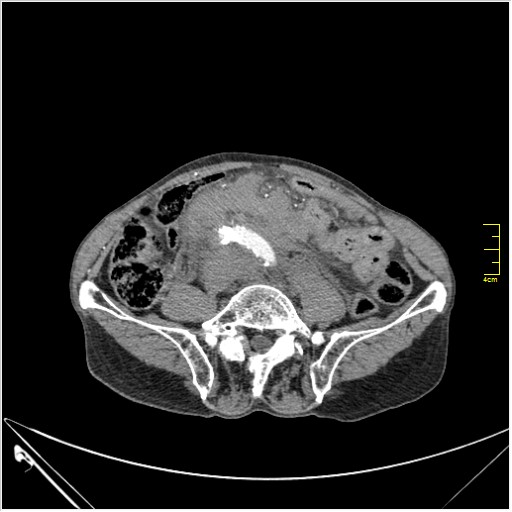

КТ брюшной полости. Мужчина с пальпируемой опухолью в животе

Пациент Т. 64 года, обратился на КТ брюшной полости амбулаторно (!), по направлению семейного врача с диагнозом abdominal mass, буквально: образование брюшной полости.